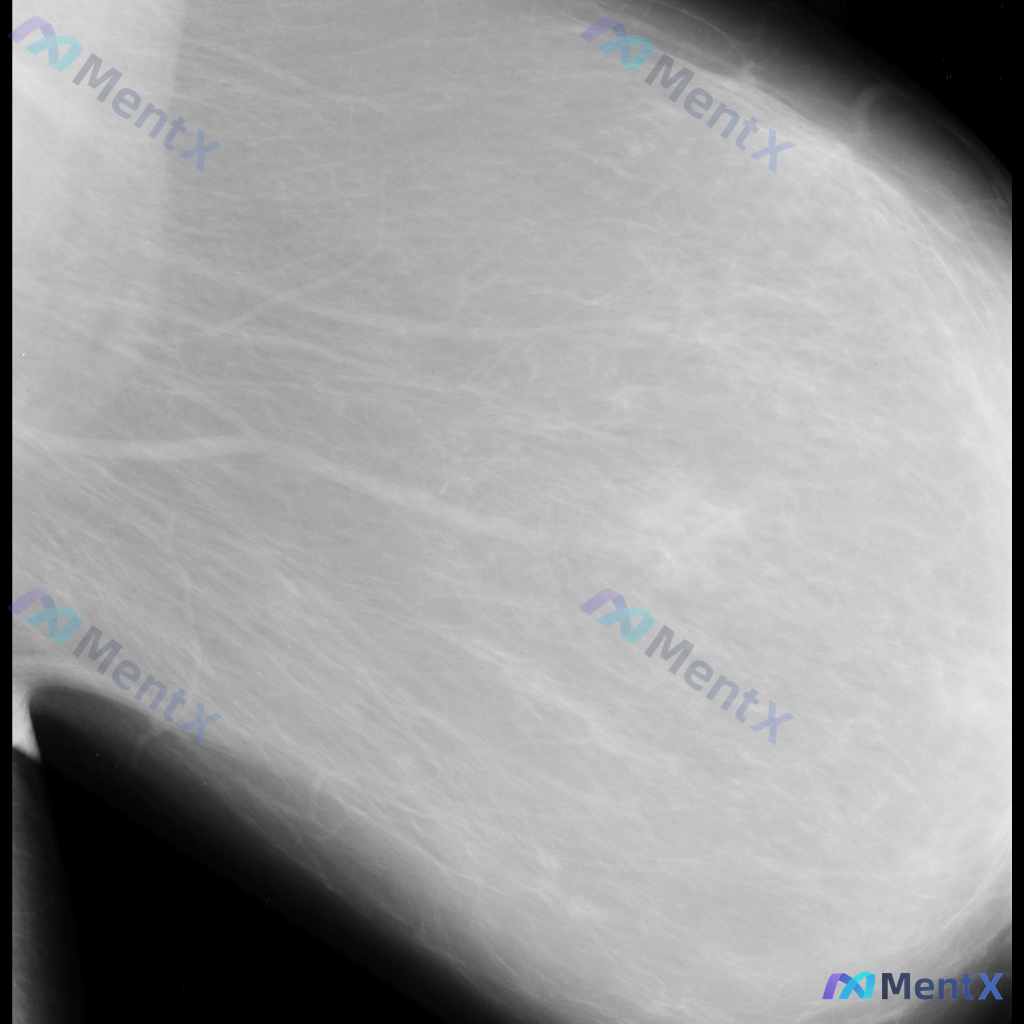

整理了一张乳腺钼靶影像的讨论资料,先和大家分享一下读片描述: 影像可见:不规则、高密度肿块/不对称致密影,伴有毛刺状边缘、结构扭曲和散在钙化。 目前考虑可能存在几种不同的异常方向,想先听听大家的第一反应——单看这组影像特征,你会先往哪种情况考虑? 也可以说说你最关注的是哪一点表现。

整理到一张单侧乳腺钼靶影像的读片资料,目前是单一体位图像,没有双侧对比。 影像表现整理 - 乳腺组织密度较高,属于多量腺体型或致密型背景 - 可见散在的钙化灶:图像中部偏下有数个点状或粗大钙化,形态不规则,但无典型恶性钙化的细小多形性、线样或分支状表现 - 乳腺下象限可见多个高密度圆形/卵圆形影,边...

整理到一份乳腺钼靶的影像资料,先和大家讨论一下读片思路。 基本影像信息 - 图像类型:单张乳腺钼靶侧位片(具体投照体位未明确,无对侧对比) - 乳腺构成:不均匀致密型(ACR C型),腺体密度较高 目前可见的影像表现 - 图像中部偏外侧的纤维腺体组织结构走行略显紊乱,但不足以诊断为明确的结构扭曲 -...